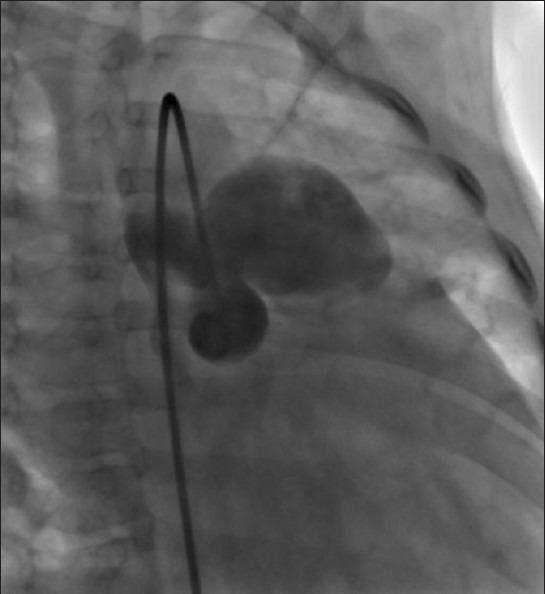

One of the rarest congenital heart diseases that results from a defect between the main pulmonary artery and the proximal aorta is named aortopulmonary window (APW). Such abnormality could be isolated, but in fifty percent of patients may be associated with other cardiac abnormalities, including arch abnormalities, specifically coarctation of the aorta, interrupted aortic arch, tetralogy of fallot, and atrial septal defect (ASD). Surgical closure or catheter-delivered devices is recommended in all patients with APW and should be performed after diagnosis as soon as possible to prevent irreversible pulmonary vascular disease. In the current era, early mortality following repair of simple APW is low and depends on the presence of associated lesions, especially interrupted aortic arch. We report an 8-month-old boy with APW who was referred to our center by respiratory symptoms and heart murmurs.